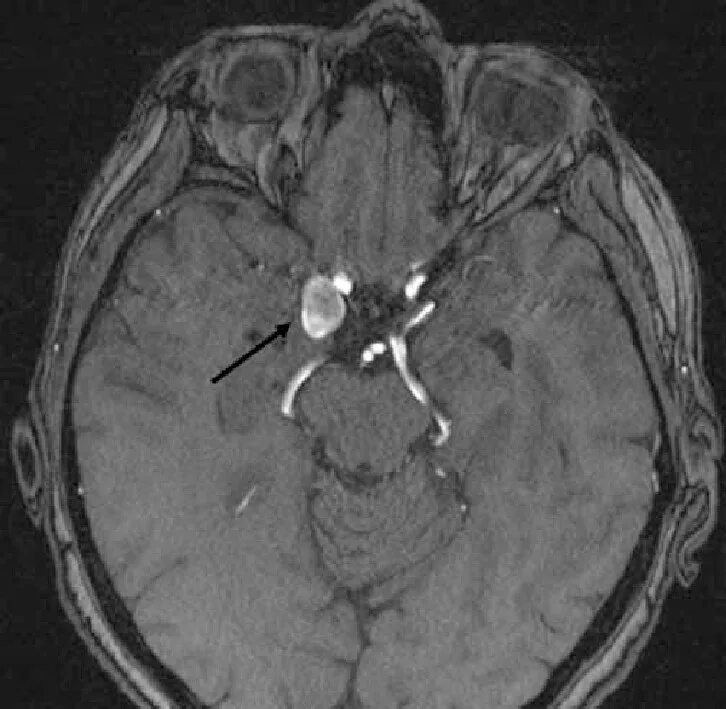

Аневризма головного мозга на кт